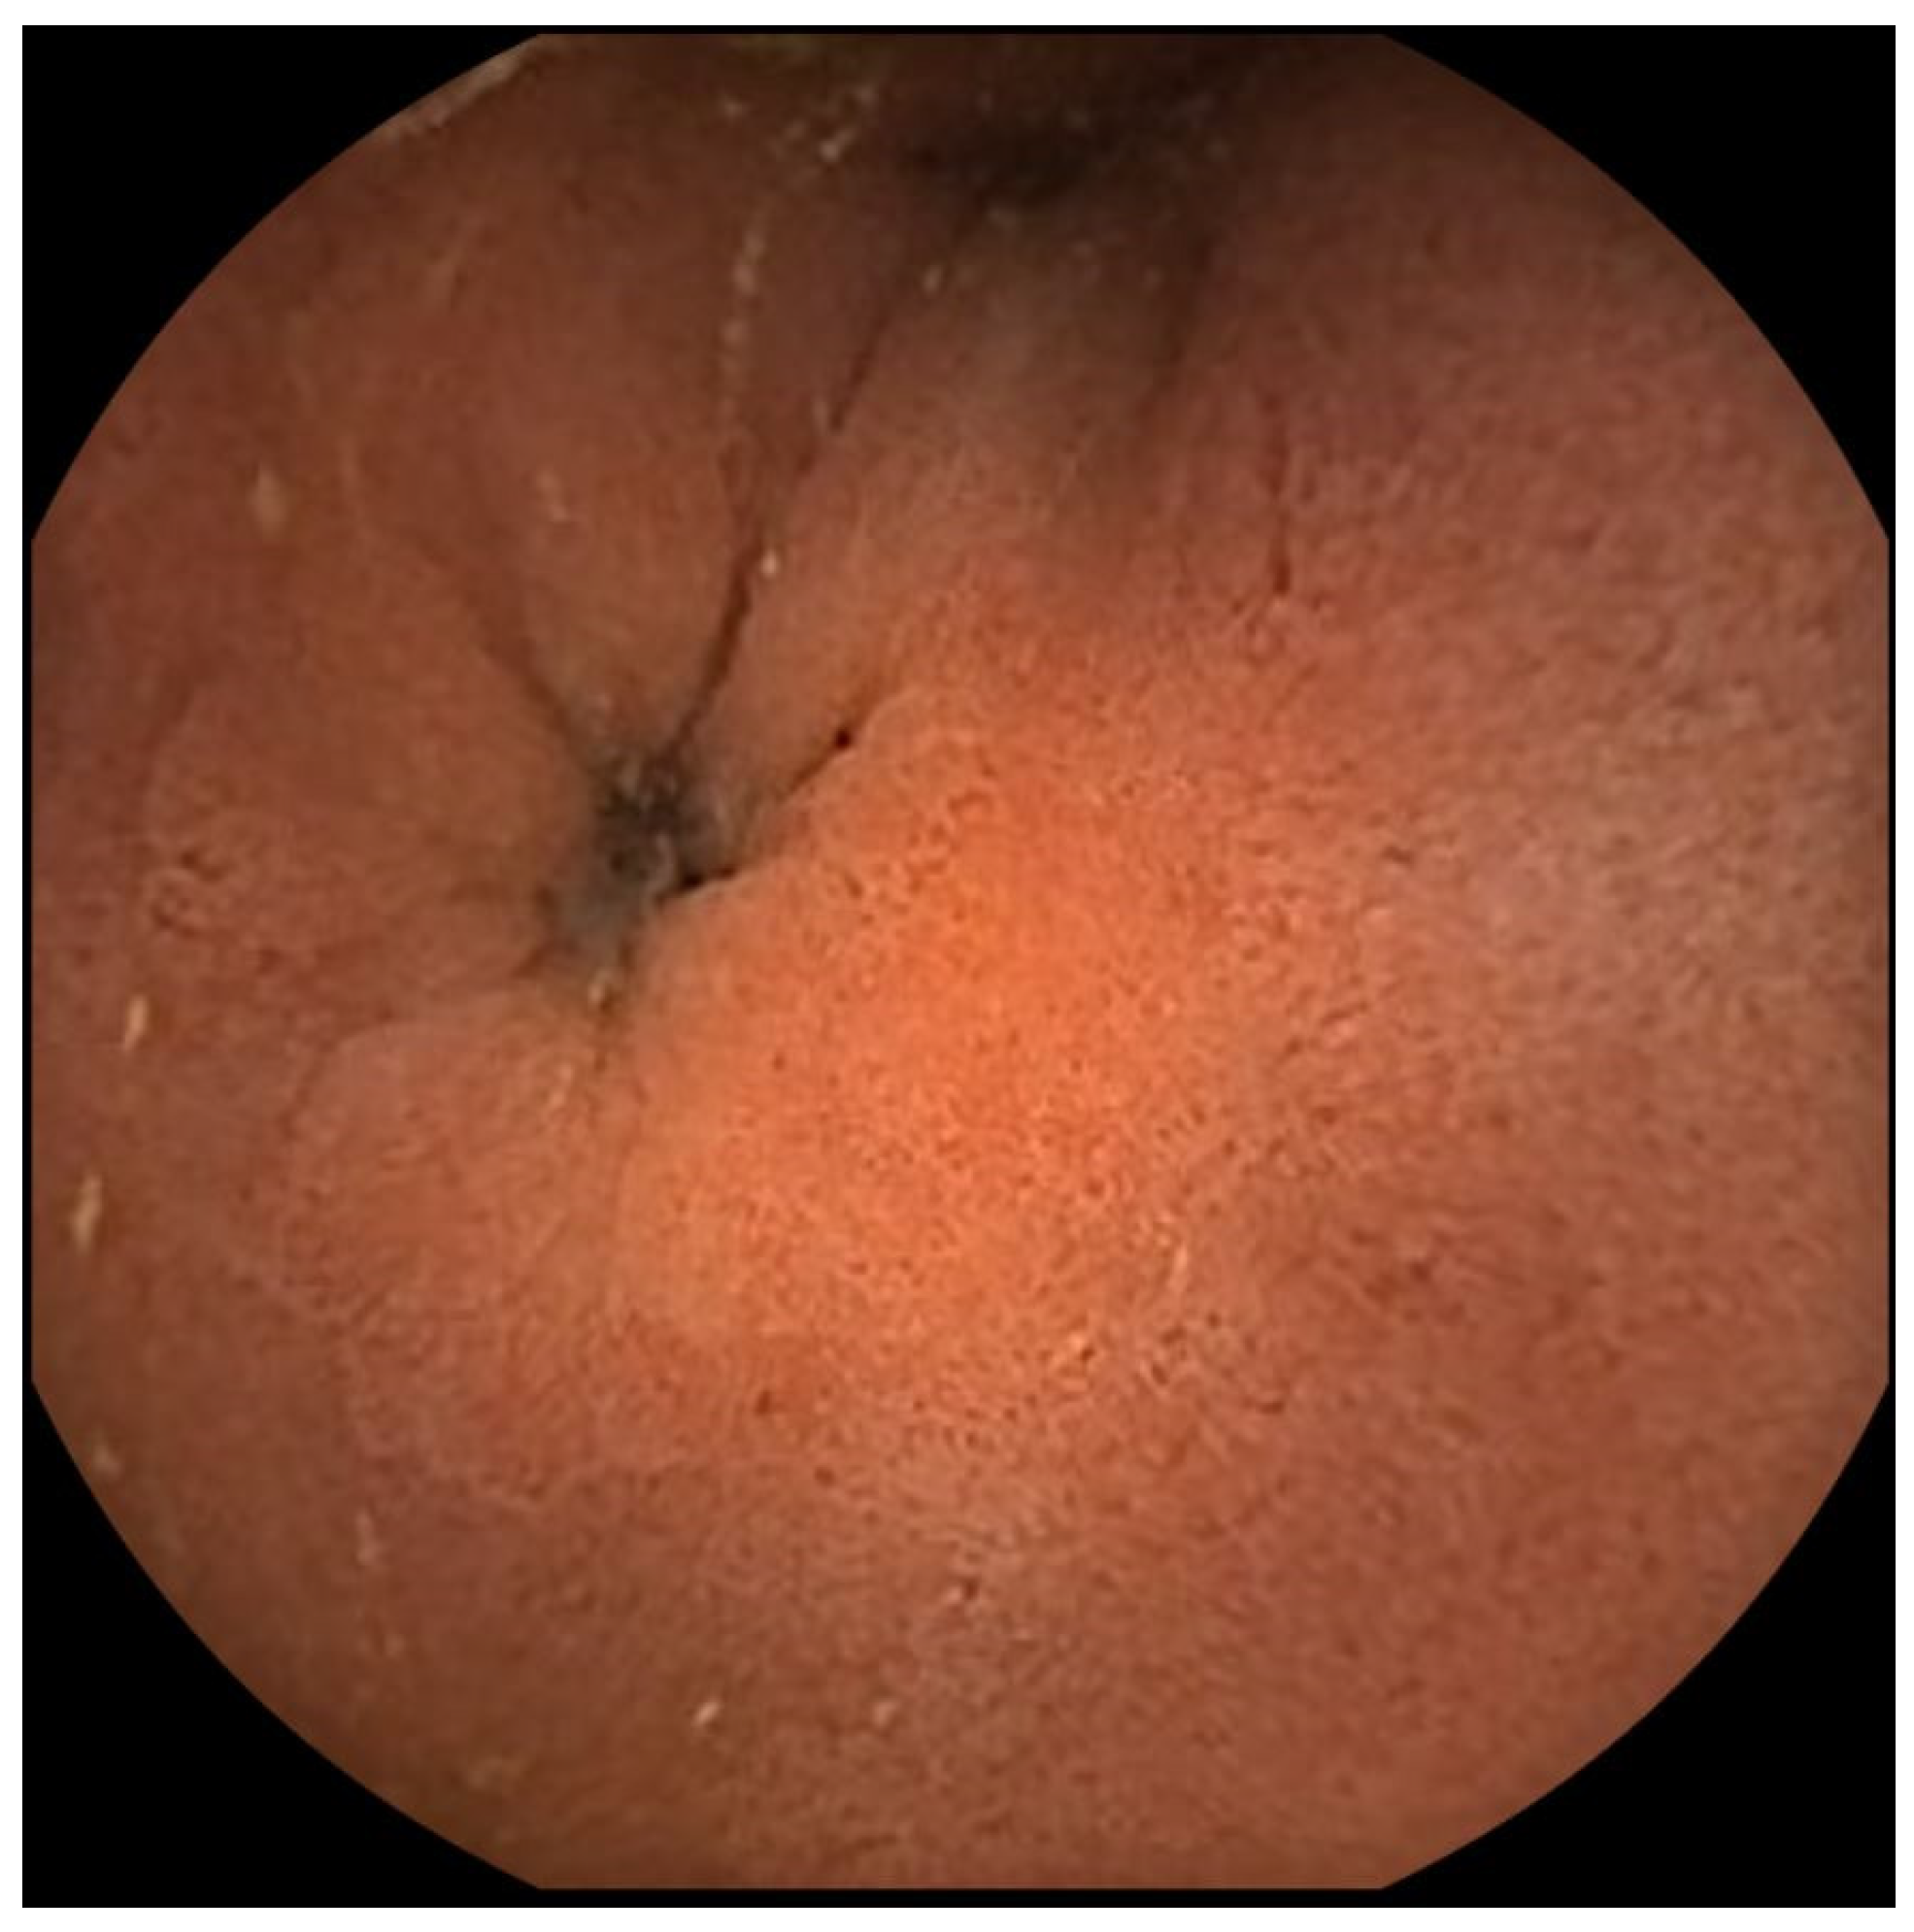

Figure A2. Normal pylorus image from the duodenal side.

In this study, we developed a deep-learning model for real-time capsule localization based on the combination of CNN and LSTM. We evaluated the performance in both research basis (accuracy, F1-score, sensitivity, and specificity) and clinical aspects (time difference between the clinician’s and model’s predictions). The model showed good sensitivity, specificity, accuracy, and F1-score of over 95% in classifying images of the stomach, small intestine, and colon. Our model also showed good performance in predicting the capsule’s entrance into the small intestine, with a mean time difference of 258 s from the clinician’s manual annotation. In the 72 cases of the total test dataset, all the model’s predictions were within 15 min, showing clinical feasibility except 3 cases. Interestingly, these three cases had some unusual features. In the two cases showing a prediction delay of 30 and 40 min for each, the capsule stayed in the duodenal bulb for a long time (around 30 and 40 min) after the entrance into the duodenum, capturing multiple pylorus images (Appendix B, also known as the dark side of the pylorus) [27], and then passed into the distal duodenum and jejunum at the time point of the model’s prediction of small intestine entrance. We assume that multiple pylorus images from the duodenal side make our model infer that the capsule stayed in the stomach. Clinically, these situations are unusual. The other case showed a 4036 s (1 h 7 min) delay in the prediction of the capsule’s small intestine entrance. In this case, the patient had previously undergone total gastrectomy, so the capsule had entered into the small intestine directly from the esophagus at 00:01:01, and then was stuck in the blind pouch for around 50 min. Except for these three unusual cases, the differences between the model’s prediction and the ground truth were within 15 min (69/72, 95.8% of the test datasets)